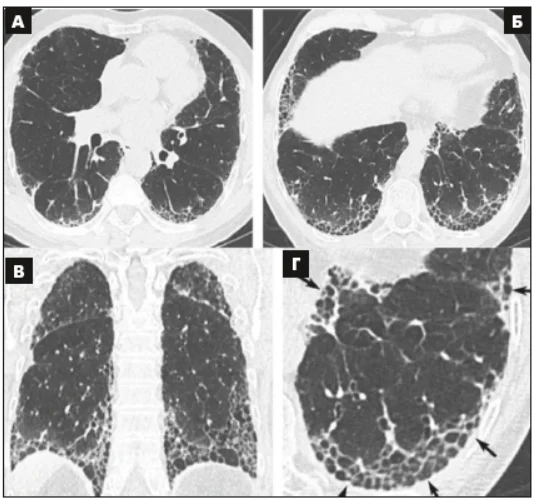

Виділено 4 діагностичні категорії, які складаються з КТ-симптомів (табл. 2 доповнена у 2022 р.). Ці категорії охоплюють ЗІП-патерн (рис. 1), імовірний ЗІП-патерн (рис. 2), невизначений (сумнівний) ЗІП-патерн (рис. 3) і альтернативний діагноз (рис. 4).

Рис. 2. КТВРЗ-патерн імовірної ЗІП.

Поперечні зрізи (A, Б), корональна реконструкція обох легень (В), збільшене сагітальне зображення правої нижньої частки (Г) ілюструють наявність ретикулярного патерну – ериферичні бронхіолоектази із субплевральним і базальним переважанням. Залежно від орієнтації відносно площини КТ-зрізу периферичні тракційні бронхіолоектази виглядають як тубулярнi (стрілки) або кістозні (наконечники стрілок) структури. Наявне помірне ПМС в субплевральних ділянках обох легень і відсутні стільникові зміни [3].